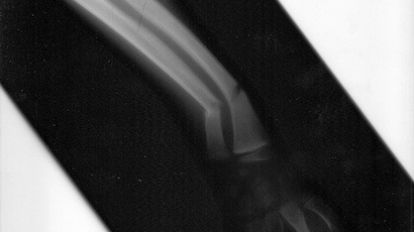

Kość złamana i nie chce się zrastać. Tymczasem ortopeda zaleca kurację ultradźwiękami, a nie skalpelem. Założę się, że początkowe zdziwienie pacjentów, których lekarz skierowałby na tego typu leczenie, ustąpiłoby rosnącemu entuzjazmowi wywołanemu efektami kuracji.

Naukowcom udało się udowodnić, że leczenie trudno gojących się złamań może być wspomagane przez specyficzny rodzaj ultradźwięków – tych o niskiej intensywności, zwanych LIPUS (Low Intensity Pulsed UltraSound). Ultradźwięki te doprowadzają do zwiększenia tzw. mineralnej gęstości kości (BMD).

Poprawę wartości wskaźnika BMD zanotowano po 16 tygodniach terapii u ponad 30% pacjentów biorących udział w doświadczeniu. Wszyscy uczestnicy eksperymentu mieli złamany trzon kości piszczelowej, wszyscy też zaliczali się do grona tych pechowych pacjentów, którym złamanie nie chciało się zrosnąć. Przedział wiekowy pacjentów był dość szeroki - od 14 do 70 lat.

Prace nad wykorzystaniem system LIPUS w leczeniu ran i w regeneracji tkanek trwają już od kilku lat. Dopiero teraz udało się jednak udowodnić, że terapia ultradźwiękowa jako metoda nieinwazyjnego leczenia złamań rzeczywiście może być skuteczna.

Skoro ultradźwięki wspomagają procesy zrastania się kości piszczelowej, można oczekiwać, że stosowanie systemu LIPUS przyniesie równie dobre efekty w przypadku leczenia innych rodzajów złamań. Tym bardziej, że wiadomo już, w czym tkwi sekret skuteczności metody: w pobudzaniu osteoblastów, czyli komórek tworzących kość.